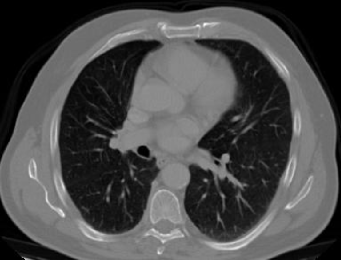

4.1.5 Chest CT

Chest CT scans play a relevant role in diagnosing a wide range of thoracic diseases, from infections to malignancies. By analyzing those scans, it is possible to detect diseases in the chest region, including pneumonia and cancer. The selected chest CT dataset 555https://www.kaggle.com/datasets/mohamedhanyyy/chest-ctscan-images contains 967 images across normal and three cancer types: adenocarcinoma, large-cell carcinoma, and squamous-cell carcinoma. Figure 6 provides a visual representation of the four highlighted classes.

Refer to caption

(a) Normal

(b) Adenocarcinoma

(c) Squamous cell carcinoma

(d) Large cell carcinoma

Figure 6: Chest CT scans.